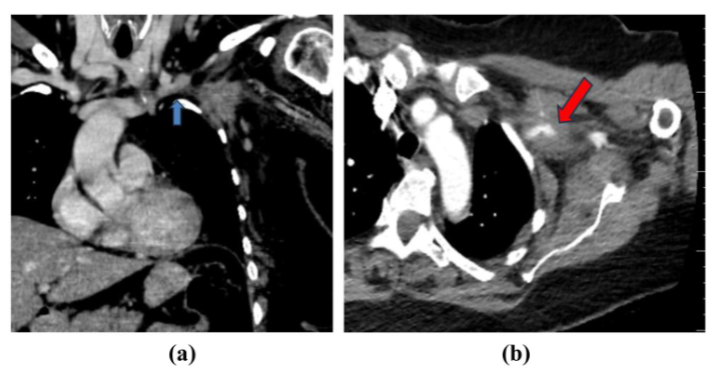

行胸部CTA提示左腋窝顶部有一38×52×58mm明显强化肿块,浸润胸小肌和肋间肌;同时可见左侧锁骨下动、静脉肿瘤浸润,节段性静脉血栓和重度动脉狭窄;腋窝处可见多发可疑肿大淋巴结,右肺上叶见一毛刺状肺结节,肝脏见乏血供病灶(倾向血管瘤表现)。

c.png图1(a)胸部CTA静脉期冠状位——箭头示左侧锁骨下静脉内血栓,与肿瘤相延续(肿瘤浸润/癌栓形成);(b)胸部CTA轴位——箭头示锁骨下/腋动脉受肿瘤包绕,血流通畅。